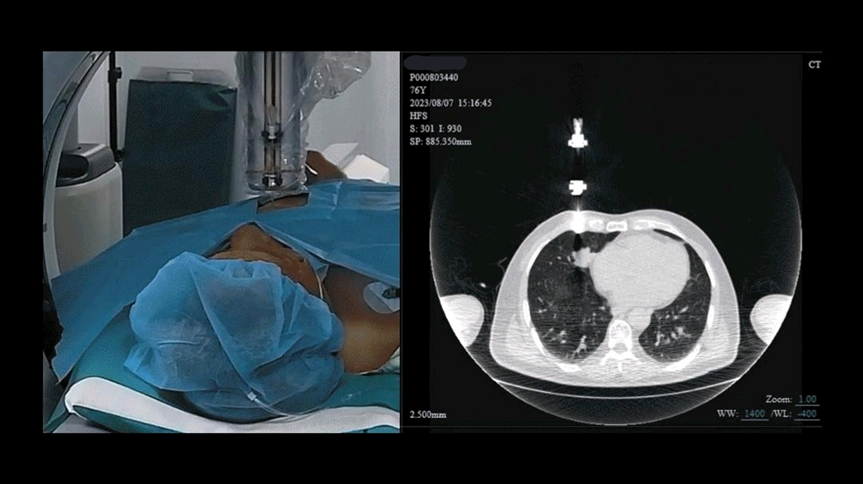

作为联影集团又一全球首创,由其子公司联影智融创新研发的CT引导经皮介入手术机器人在大会中赢得广泛关注。该机器人实现了临床术式的革命性突破,让医生能在动态CT实时影像引导下“边看边穿”,并能隔室操控手术机器人,完成穿刺全过程,大幅提升手术的精准性与安全性,引领经皮介入临床诊疗进入CT“实时可视化”时代。

CT引导经皮介入手术机器人凭借原研“黑科技”,真正做到了“实时可见”。据联影智融放射介入产品业务总经理毛毅君介绍,全套方案由手术间和操控间构成,机器人的uReal-time®科技利用高速双向流处理技术,在操作间和手术间搭建了毫秒级的CT实时影像传输和手术器械远程控制的双向同步信息快车道,提供精确的实时引导,使医生能稳坐CT扫描间外控制穿刺器械实时追踪肿瘤位移,精准直达靶点。

什么是联影ctCT引导介入手术边看边穿!联影集团又一全球首创_https://www.jmylbn.com_新闻资讯_第6张经皮介入手术机器人可视化引导安全进针

机器人的另一项“黑科技”——uReal-space™通过生成式智能技术,能解构医生精细的手术操作,控制亚毫米级医用机械臂的360度精准运动和穿刺,其前沿触觉感知技术能真实还原手术沉浸感,大幅提升了手术的安全性。

既看得见,又穿得准。医生在操作间内就能实时控制进针过程,既能降低因为“穿刺过程不可见”带来的对危险组织误穿刺的概率,又能减少因反复进针和调整带来的并发症风险和痛苦。